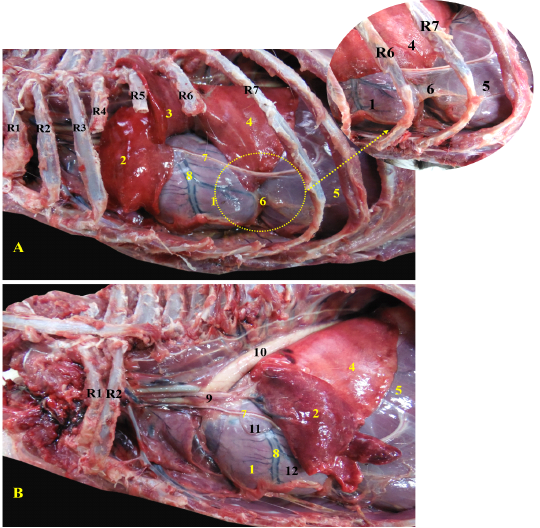

Showing the heart of red fox insitu A- showing the heart insitu after rib reflection, B - showing the heart after reflection of the left cranial lobe of lung.